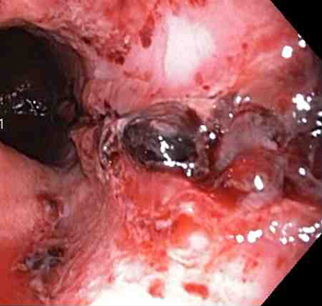

A mechanical method (e.g., clips) with or without adrenaline (epinephrine). In practice, both through-the-scope clips (TTSC) and over-the-scope clips are options depending on availability and expertise. However, for MWT, TTSC usually suffice.[Figure caption and citation for the preceding image starts]: Mallory Weiss tear after application of through-the-scope clip results in haemostasisFrom the personal collection of Douglas Adler; used with permission [Citation ends].

Mallory Weiss tear following cauterisation with a bipolar probeFrom the personal collection of Douglas Adler; used with permission

TTSC use is as safe and effective as other methods for controlling actively bleeding lesions.[76][77][78][Figure caption and citation for the preceding image starts]: Mallory Weiss tear after application of through-the-scope clip results in haemostasisFrom the personal collection of Douglas Adler; used with permission [Citation ends].